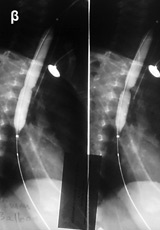

ΙΙΙ. Η μέθοδος της εντερόκλυσης είναι μία ουσιαστική κατάκτηση που ενισχύει

το απεικονιστικό οπλοστάσιο. Η φιλοσοφία της εξέτασης έγκειται στη γρήγορη έγχυση

σκιαγραφικού π.χ. βαρίου ή μεθυλκυτταρίνης απ' ευθείας στο σύνδεσμο του TREITZ

μέσω ενός ακτινοσκιερού καθετήρα (πίνακας ΙΙΙ).

Η μαγνητική εντερόκλυση είναι μία πολλά υποσχόμενη μέθοδος για την απεικόνιση

των παθήσεων του λεπτού εντέρου. Από τη μέχρι τώρα κλινική εμπειρία προκύπτει

η μεγάλη διαγνωστική της αξία στη νόσο του Crohn, τα νεοπλάσματα του λεπτού

εντέρου και στην εντερική απόφραξη. Η μέθοδος είναι χρήσιμη για την παρακολούθηση

ασθενών με νόσο Crohn, απεικονίζει με εξαιρετική ευκρίνεια σημεία απόφραξης

και αποτυπώνει μικρά συρίγγια ή συριγγώδεις πόρους που δεν μπορούν να ανιχνευθούν

με ακρίβεια στη συμβατική εντερόκλυση (εικόνα 9).